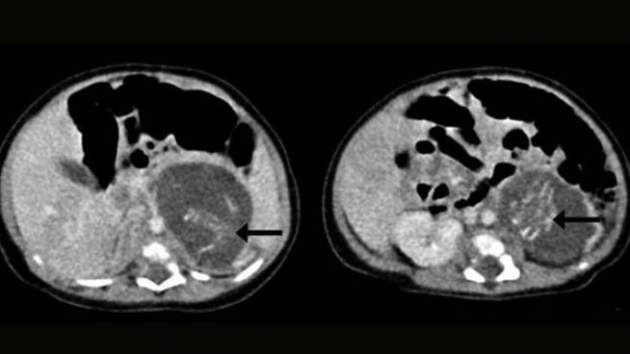

Se da en uno de cada 500.000 nacimientos y se conoce en términos médicos como ‘fetus in fetu’. Ha sido en Hong Kong (China) donde se ha diagnosticado el último caso de este acontecimiento tras encontrársele a una bebé de tres semanas dos fetos de mellizos en el vientre. El ‘fetus in fetu’ suele producirse por un fallo en la formación del cigoto antes de la formación del embrión, lo que conlleva que rara vez tenga órganos internos funcionales. En el caso aparecido en China, los fetos, de ocho y diez semanas de gestación, tenían formadas las piernas, los brazos, la columna y parte de los intestinos.

Los fetos le fueron extirpados a la bebé, que fue dada de alta del hospital ocho días después. El caso, por su carácter extraordinario, se detalla en el último número de la revista Hong Kong Medical Journal, donde se especifica que solo se conocen unos 200 casos en todo el mundo de ‘fetus in fetu’.